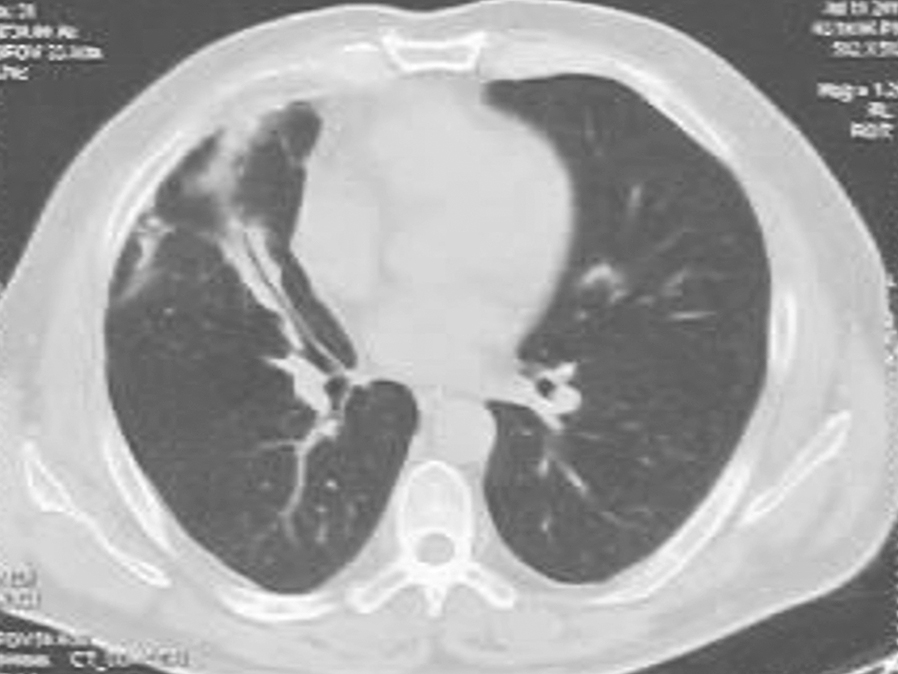

图3 胸部CT表现(2011-02-09)

胸部CT可见右肺实变影较前增大,并出现不规则厚壁空洞